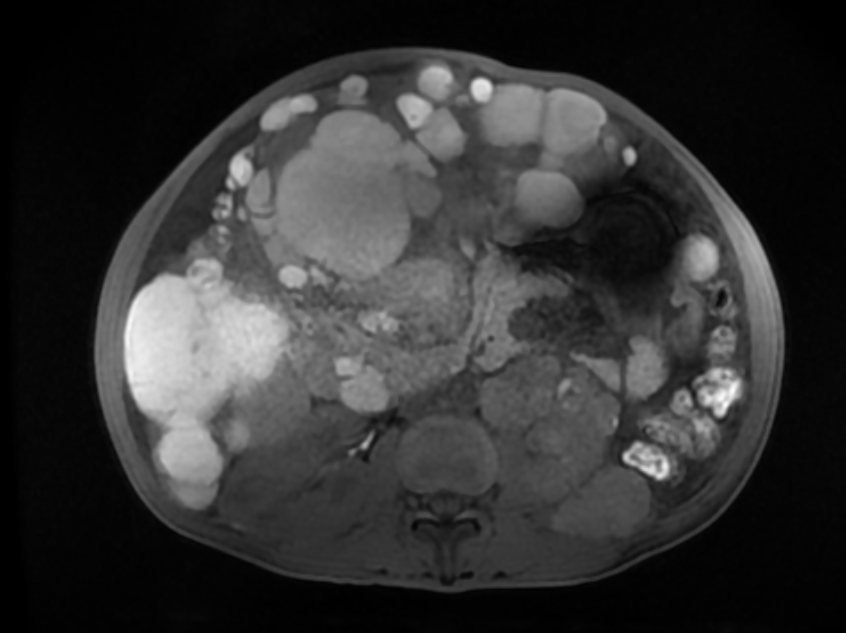

随后的腹部MRI显示,患者腹内存在大面积肿瘤。黄广优介绍,肿瘤面积极大,已侵犯腹内多个器官,造成了严重器官功能损害,因此,何女士出现了腹痛、体力下降、双下肢水肿等症状。“再不治,很可能活不过三个月。”黄广优说。

MRI显示,患者腹内存在大面积肿瘤